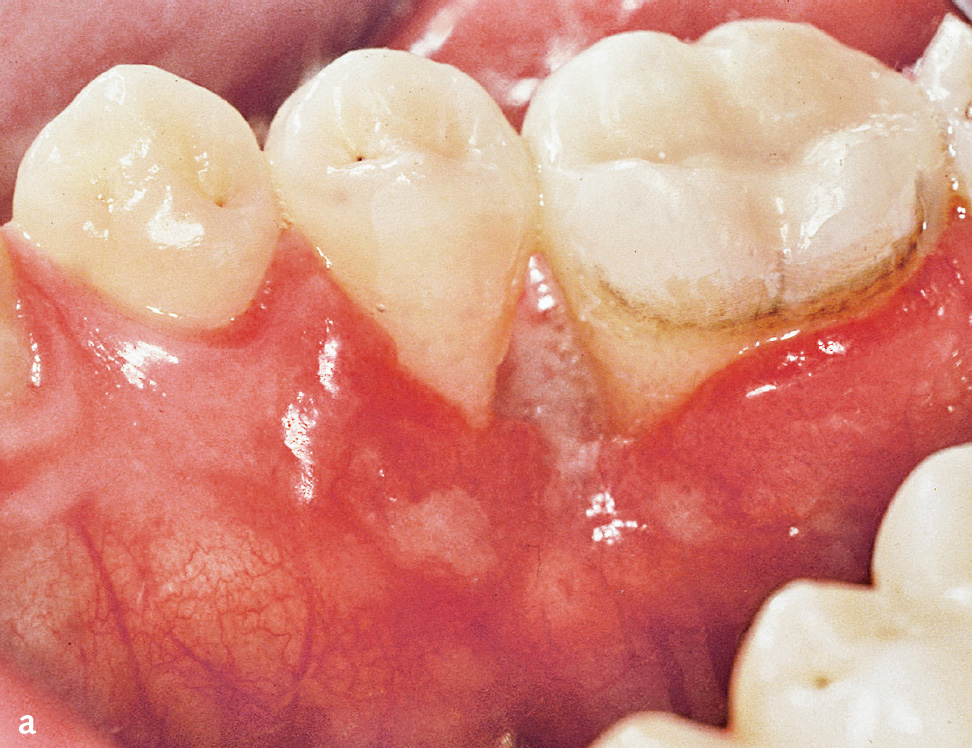

Läsionen können auch intraoral auftreten und klinisch das Erscheinungsbild einer rasch verlaufenden oder nekrotisierenden Parodontitis annehmen14 (Abb. 3a und b).

Abb. 3a und b 24-jähriger männlicher Patient mit oralen Manifestationen einer Langerhans-Zell-Histiozytose (eosinophiles Granulom) approximal der Zähne 35 und 36: a) klinische Ansicht; b) Röntgenbild mit approximalem Knochenabbau (Abbildungen aus Kugel et al. 20015).